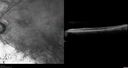

82 year old man with a sister with RP and no other family members. He has trouble with night vision. VA 20/25 OD, 20/32 OS. Note the symmetry in the FAF images typical for a dystrophy. The photos show bone spicules, arteriol attenuation and optic nerve pallor

Retinitis Pigmentosa - Autosomal Recessive - 82 year old man with Good Vision450 viewsVA 20/25, 20/32 - Bone spicules in periphery - FAF is very symmetric     (0 votes)